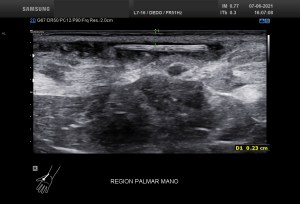

La imagen 3 y 4, como son tan nítidas, puedes ver como el quiste de Baker no es un quiste de Baker simple, la pared es grosera, tiene septos y ecoestrusturas que hacen pensar que el quiste ha podido sufrir algún sangrado. Hay que descartar la formación de lesiones sólidas o polos sólido en los quistes (usando doppler), por norma general, en todos aquellos quistes que estudiemos, en otras localizaciones, por ejemplo, en la mama, en el abdomen, etc.